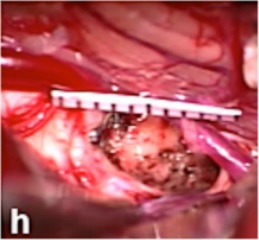

圖a:術(shù)前6個(gè)月MRI顯示輕度出血

中腦海綿狀血管瘤